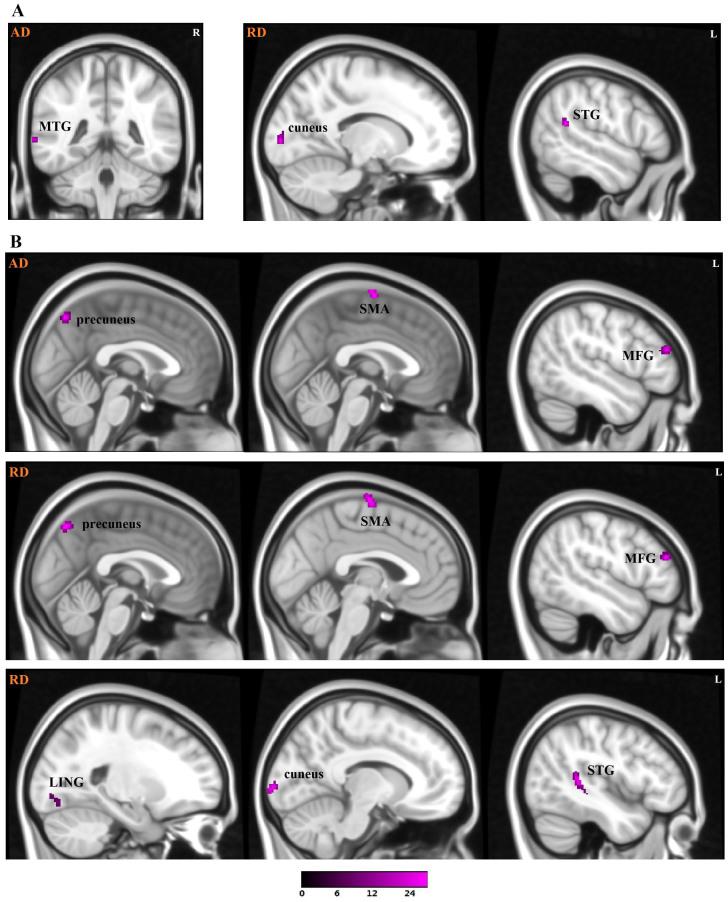

Previous research has demonstrated that there are specific white matter abnormalities in patients with attention deficit/hyperactivity disorder (ADHD). However, the results of these studies are not consistent, and one of the most important factors that affects the inconsistency of previous studies maybe the ADHD subtype. Different ADHD subtypes may have some overlapping microstructural damage, but they may also have unique microstructural abnormalities. The objective of this study was to investigate the microstructural abnormalities associated with two subtypes of ADHD: combined (ADHD-C) and inattentive (ADHD-I). Twenty-eight children with ADHD-C, 28 children with ADHD-I and 28 healthy children participated in this study. Fractional anisotropy (FA), radial diffusivity (RD) and axial diffusivity (AD) were used to analyze diffusion tensor imaging (DTI) data to provide specific information regarding abnormal brain areas. Our results demonstrated that ADHD-I is related to abnormalities in the temporo-occipital areas, while the combined subtype (ADHD-C) is related to abnormalities in the frontal-subcortical circuit, the fronto-limbic pathway, and the temporo-occipital areas. Moreover, an abnormality in the motor circuit may represent the main difference between the ADHD-I and ADHD-C subtypes.

先前的研究表明,注意缺陷多动障碍(ADHD)患者存在特定的白质异常。然而,这些研究的结果并不一致,影响先前研究不一致性的最重要因素之一可能是ADHD亚型。不同的ADHD亚型可能存在一些重叠的微观结构损伤,但也可能有独特的微观结构异常。本研究的目的是调查与ADHD的两种亚型相关的微观结构异常:混合型(ADHD-C)和注意力不集中型(ADHD-I)。28名ADHD-C儿童、28名ADHD-I儿童和28名健康儿童参与了本研究。采用分数各向异性(FA)、径向扩散率(RD)和轴向扩散率(AD)分析扩散张量成像(DTI)数据,以提供有关异常脑区的具体信息。我们的结果表明,ADHD-I与颞枕区异常有关,而混合型(ADHD-C)与额-皮质下环路、额-边缘通路和颞枕区异常有关。此外,运动环路异常可能是ADHD-I和ADHD-C亚型之间的主要差异。